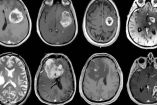

EU deporta a niña con cáncer cerebral; viajaba por tratamiento

La niña, que aún lucha contra los efectos de una cirugía para extirpar un tumor, fue detenida junto a su familia en un puesto de control migratorio.